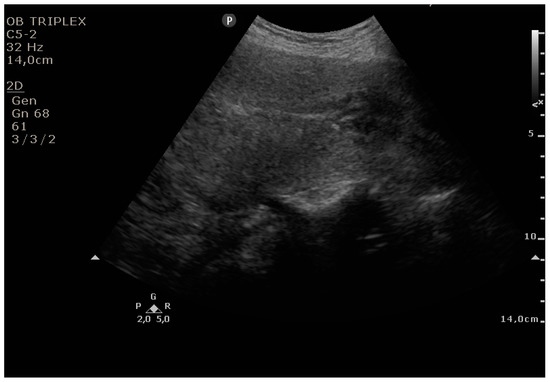

The PUUS method evaluates the proportion of the endometrial length occupied by blood or debris, as follows (Figure 1, Figure 2, Figure 3, Figure 4 and Figure 5):

Grade 0: no blood or debris in the uterine cavity;

Figure 1. Grade 0: no blood or debris in the uterine cavity.